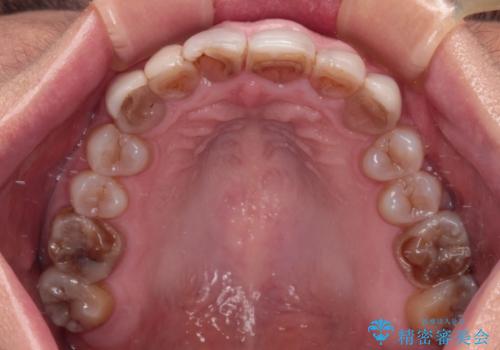

上顎前歯は樹脂による変色を覆い隠す処置が行われていましたが、汚れが溜まりやすく厚みも増している状態でした。

上顎前歯は樹脂を外し、下顎前歯の隙間はそれぞれの歯を大きくするように補綴治療を行うことで隙間を埋めることとしました。